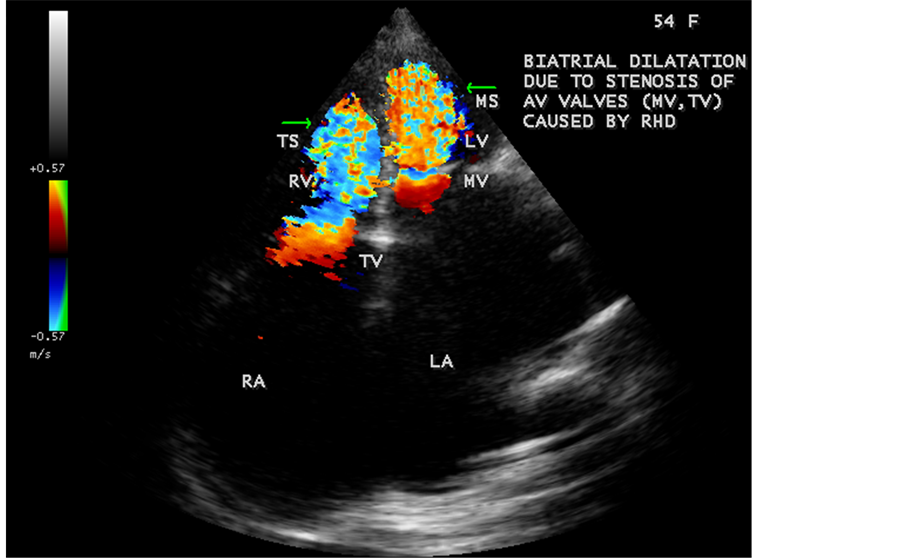

Figure 56. Biatrial enlargement in a 54-year-old female due to rheumatic AV (atrioventricular― mitral, tricuspid valves) involvement mimicking biatrial enlargement due to EMF as shown in Figure 33.

Figure 57. Biatrial enlargement due to rheumatic AV (atrioventricular) valve stenosis (mitral stenosis, tricuspid stenosis)―in contrast to EMF as shown in Figure 34 which is associated with AV valve regurgitation.